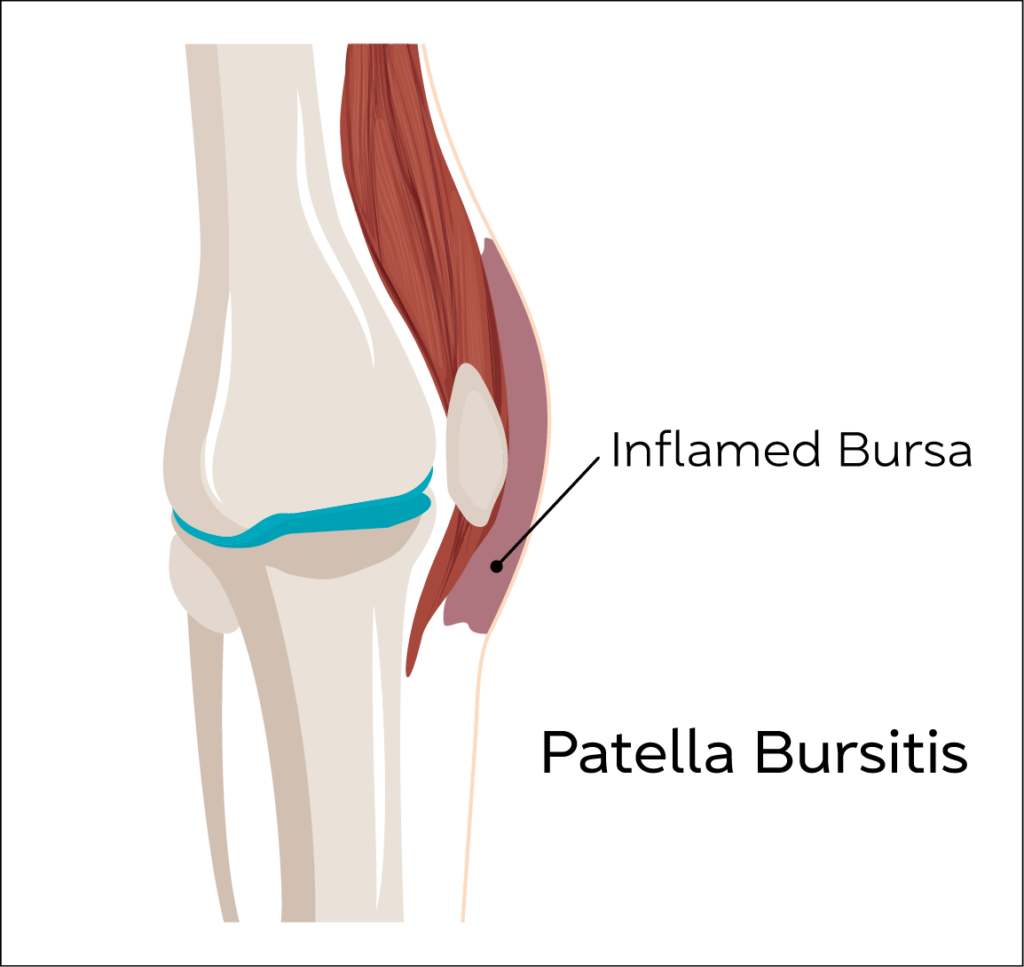

Patella Bursitis (Supra/Pre/Infra)

Inflammation of normal fluid filled spaces around the knee joint.

Patella Bursitis can be common in people with repetitive work tasks that result in kneeling for prolonged periods.

Common symptoms of patella bursitis are pain during activity, rapid swelling in the front of the kneecap, tenderness and a slight rise in temperature of the area.

If symptoms are not relieved with simple anti inflammatory medications and activity modification, ultrasound guided aspiration followed by steroid injections have proven to give relief of symptoms